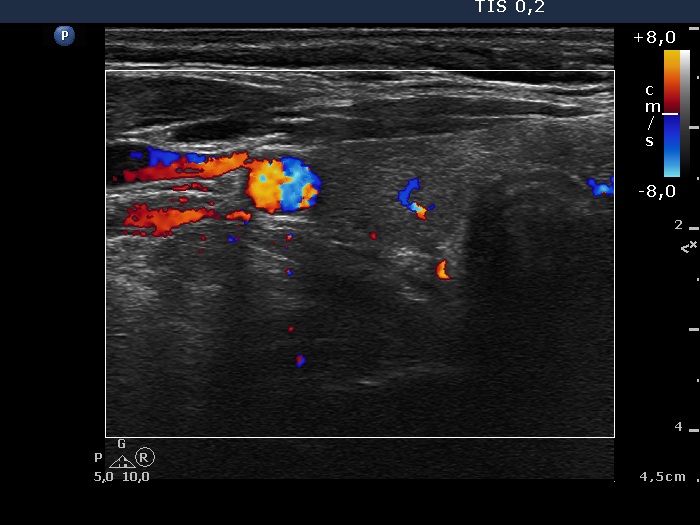

Ultrasonography. The thyroid was echonormal. There was a small, moderately hypoechogenic nodule in the right lobe, while the left lobe contained multiple nodules with different echogenicities.

The moderately hypoechogenic nodule in the lower pole of the right thyroid was aspirated. We gave a combined cytological-ultrasound diagnosis of benign follicular proliferation.